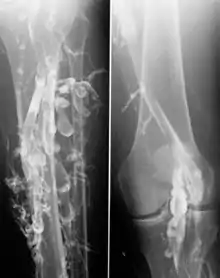

- Артеріальні захворювання:

- Артеросклероз та його ускладнення

- Аневризми

- Травми судин

Іноді ангіографію використовують, щоб побачити хід важливих судин при плануванні операції .